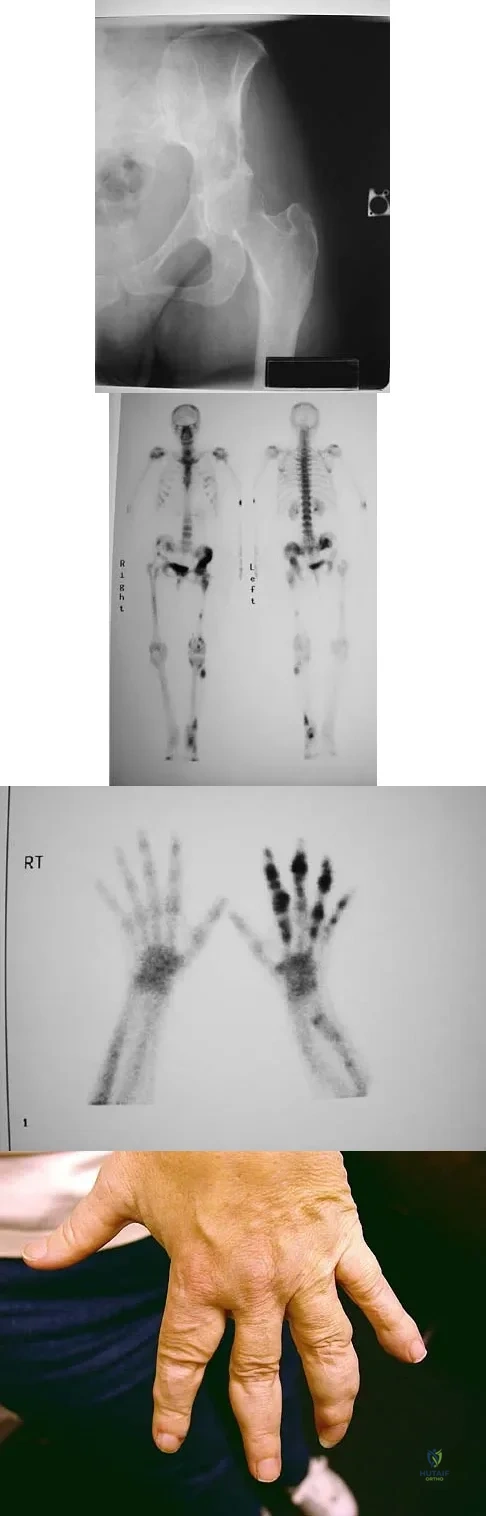

Question 34

Figure 15a shows the radiograph of a patient who has a chondrosarcoma of the acetabulum. Bone scans are shown in Figures 15b and 15c. Numerous soft subcutaneous masses are present. A clinical photograph of the hand is shown in Figure 15d. What is the most likely diagnosis?

Explanation